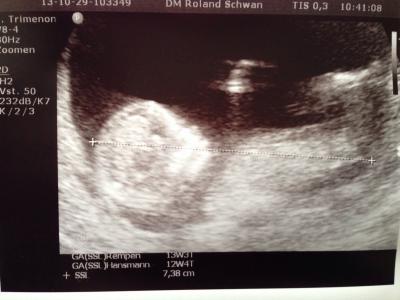

Hallo Mädels, hatte heut die Nackenfaltenmessung und ich bin sehr erleichtert das alles gut ist. Das kleine hat so rambazamba gemacht, es hat sich von allen Seiten gezeigt. Bin sehr glücklich und es ist auch beim zweiten Kind wieder so spanend und rührend. Termin bleibt der 5.5.14

Bild zu FA heute - Forum für Mai - Mamis